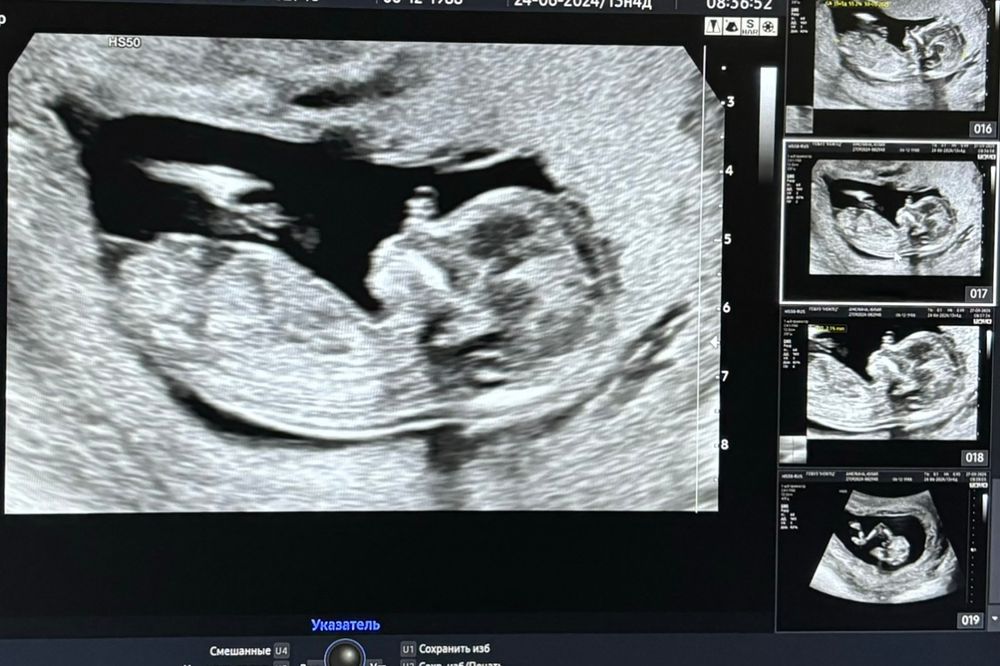

1 скрининг,полёт нормальный😎👍

Ходили с мужем. С малышариком всё хорошо,это самое главное 🙏Врач подтвердила что мальчик 👦 Хотя я просто спросила видно ли пол на этом сроке,она сразу ответила «мальчик у вас» и даже показала все причиндалы😉 Боже,я не могу поверить,я буду мамой 4 деток! Это такое счастье 🥹🙏🙏